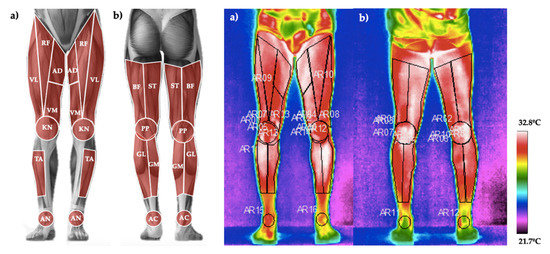

2.3.2. Skin Temperature